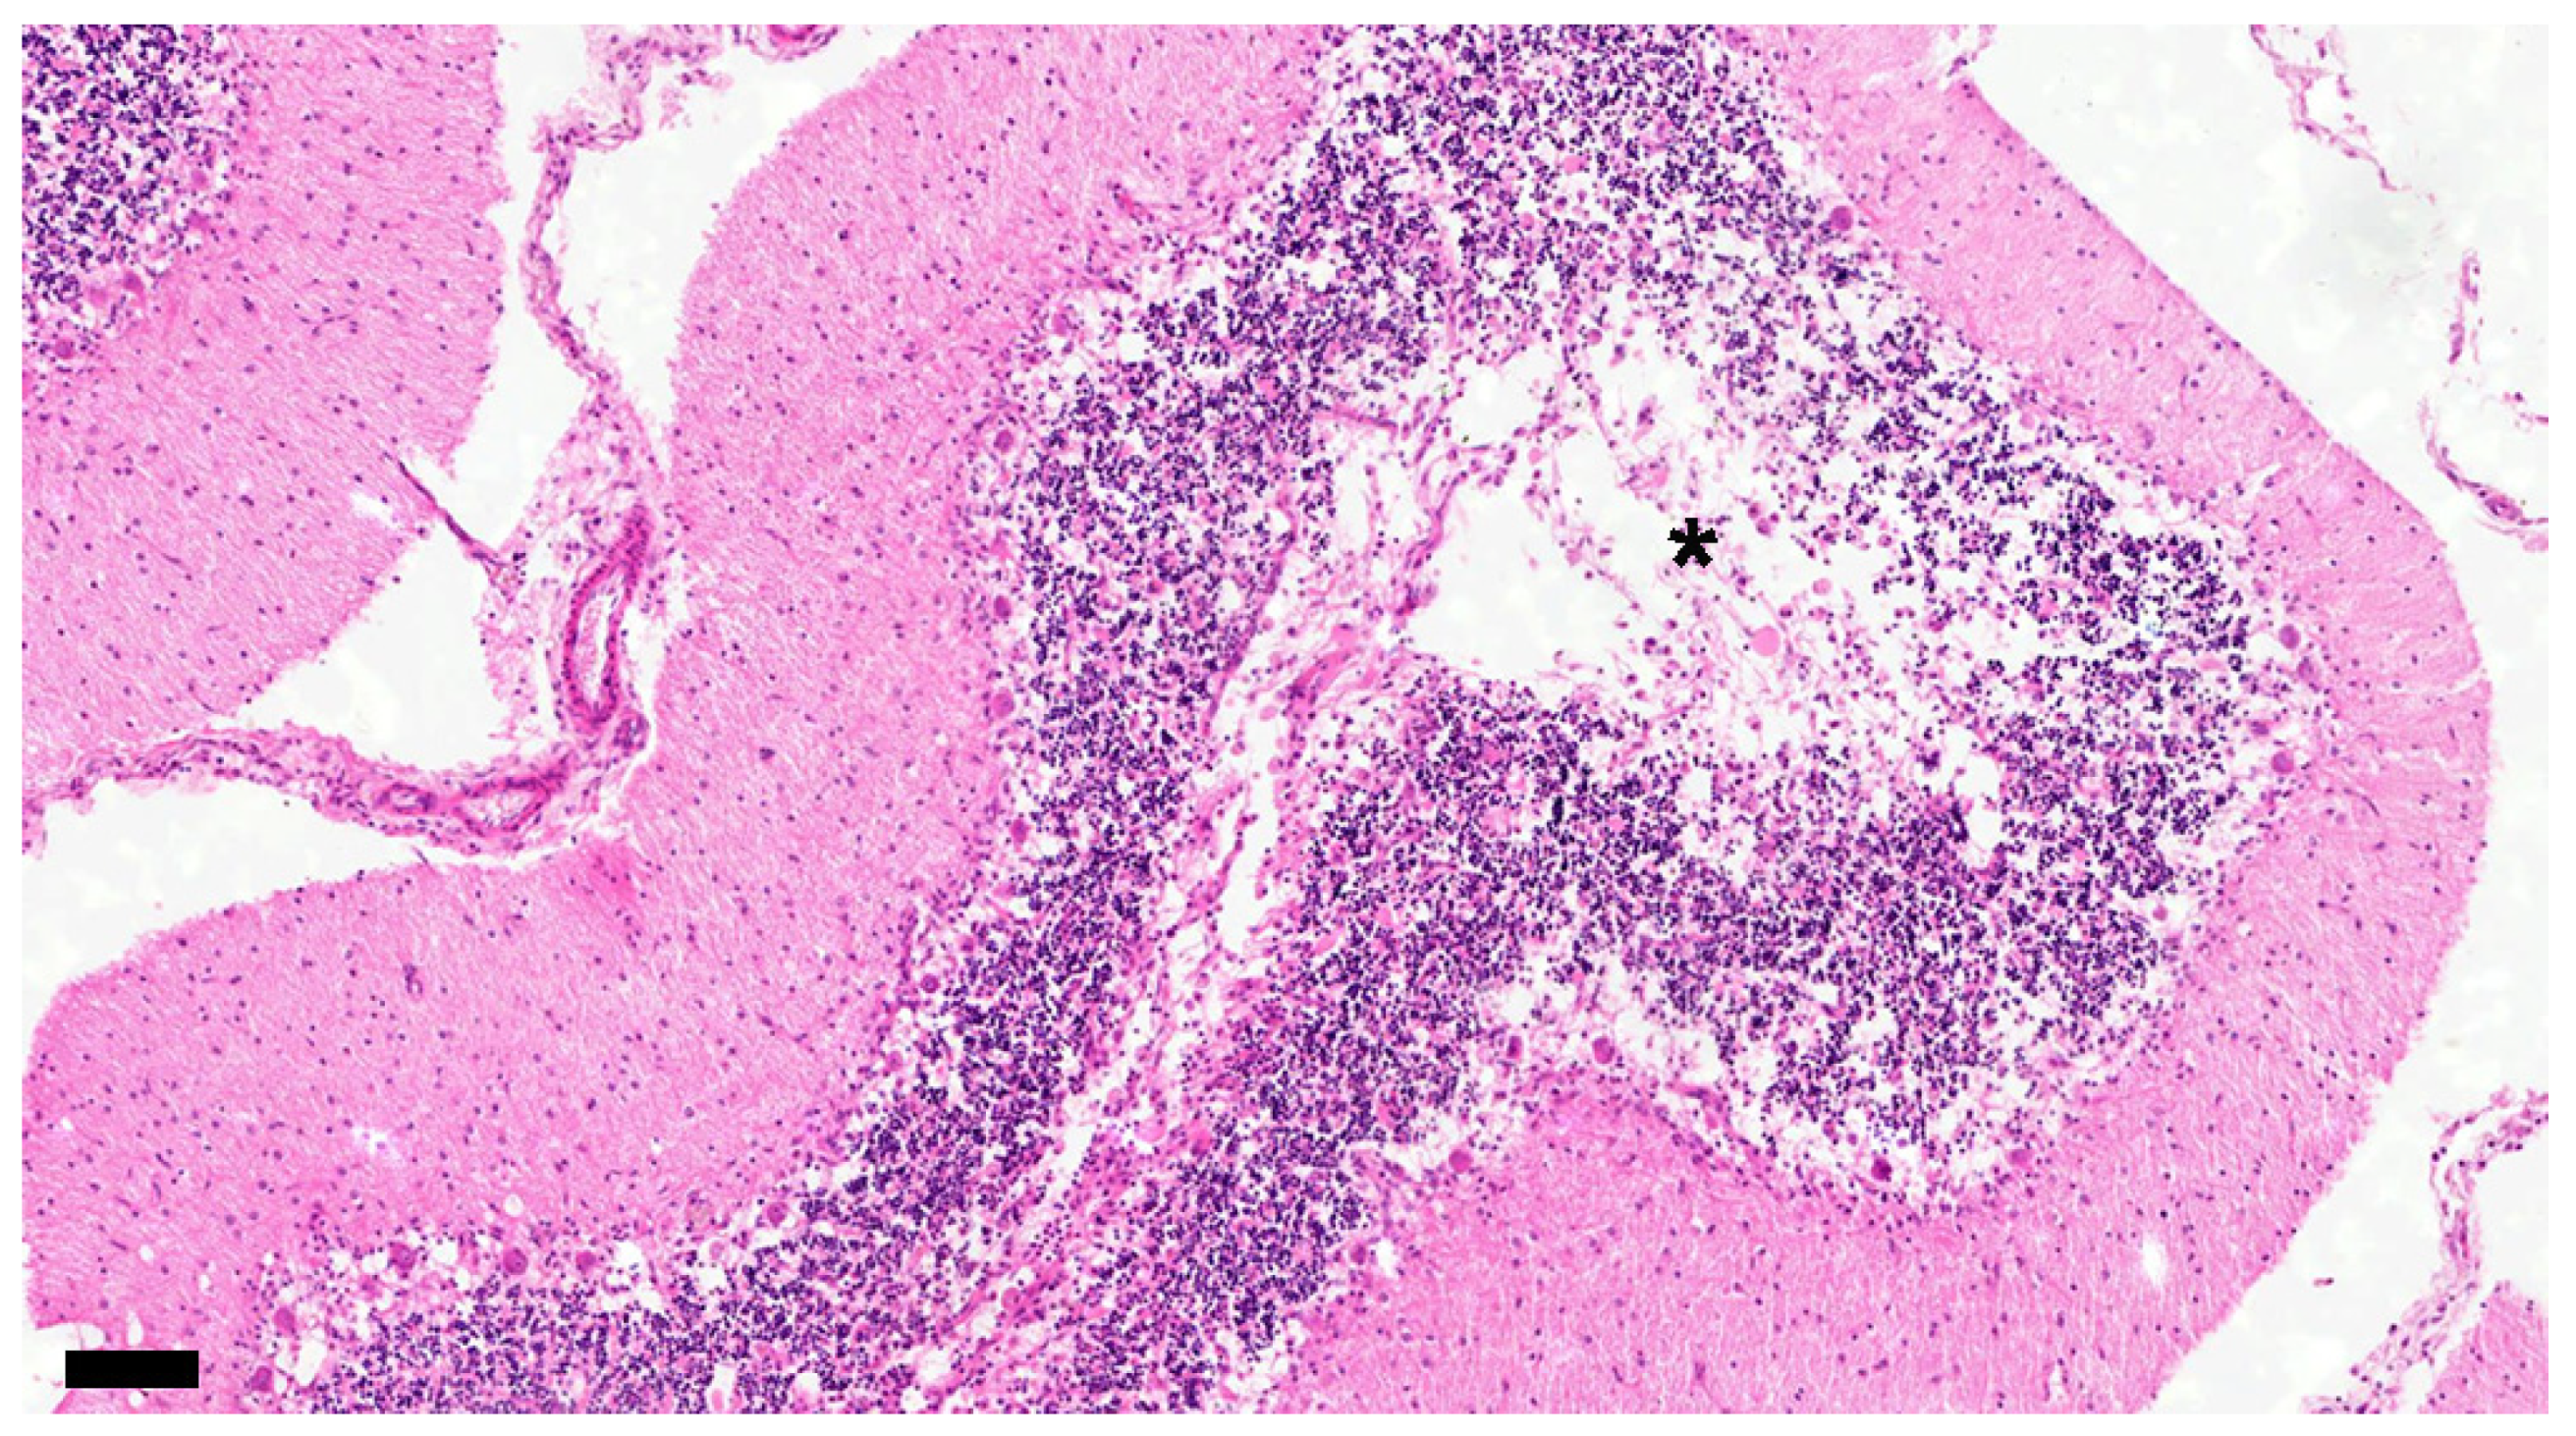

| Subacute 2 | 9 | (2 months old–10 years old) | demyelination, glial cell reaction, inclusion bodies, CDV-immunoreactive particles, meningitis, mild decreased granular layer cells, and Purkinje cells |

| Subacute 3 | 5 | (3 months old–3 years old) | demyelination, glial cell reaction, inclusion bodies, CDV-immunoreactive particles, meningitis, moderate decreased granular layer cells, and Purkinje cells |

| Chronic | 6 | (3 months old–3 years old) | demyelination, gliosis, glial cell reaction, inclusion bodies, CDV-immunoreactive particles, meningitis, severe decreased granular layer cells, and Purkinje cells |